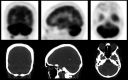

A 47-year-old woman presented with an acute cerebellar syndrome. Neither cerebellar atrophy nor an infarction or tumor was shown on MRI. A diagnostic CT demonstrated enlarged axillary lymph nodes, but no primary tumor. Puncture of these nodes showed non-small cell carcinoma. 18F-FDG PET/CT imaging was performed and suggested an occult breast carcinoma, which was confirmed by pathological examination. It also showed cerebellar hypermetabolism, consistent with a PCS (paraneoplastic cerebellar syndrome). This case shows that 18F-FDG PET imaging may be of value in patients in which a PCS is considered clinically, particularly in patients suspicious for an occult malignancy.